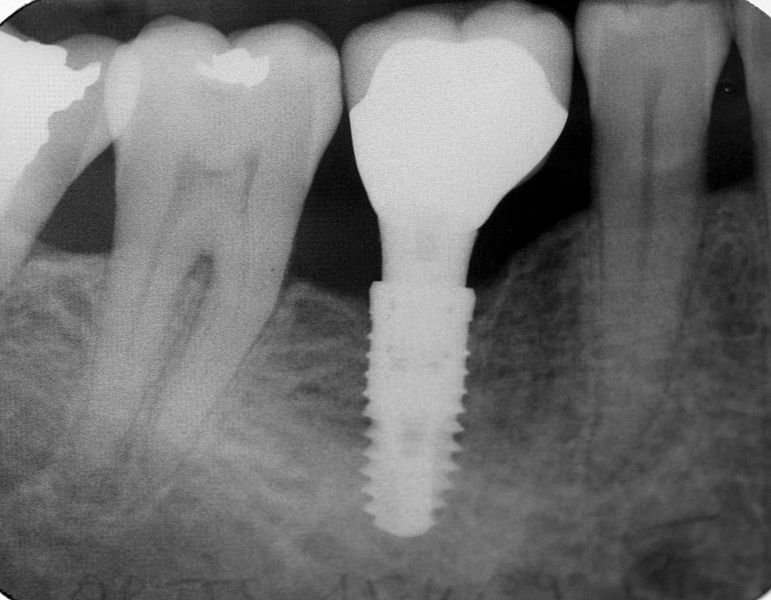

Your dentist will work very closely with you to create an overall treatment plan. The first step is to put the root of the dental implant into the place where your missing tooth was. Your jaw and gums will heal around the implant over the course of 2-3 months.

This procedure can be done in one or two stages, depending on how much gum and bone damage you have. In the one-stage procedure, you receive a healing cap to cover the space while the bone heals. After you’re healed, you get your permanent cap or crown.

The two-stage procedure is normally performed when a person need a bone graft or regeneration work. When this happens, you end up with stitches to close the gum so that the bone can heal. Then you come back for a 2nd trip to have an incision made into the gum line again. Once the gum heals, you can move on to the permanent crown.

Once your jaw is healed, your dentist will make an impression of your mouth so that your new crown matches your other teeth as closely as possible. Once finished, you’ll look and feel as though you have a permanent tooth in your mouth.